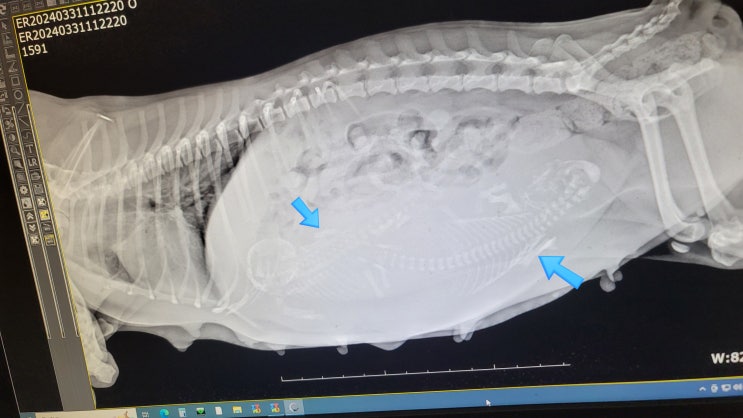

미니비숑 출산했어요 강아지 제왕절개 겨울이 엄마되기 part.3

우리 집 반려견 미니비숑 겨울이가 드디어 출산을 했어요! 사실 이 포스팅은 과거 약 5개월 전의 상황이다 ...

미니비숑 임신 그리고 강아지 출산준비물 엄마되기 part.2

우리 집 반려견 겨울이 미니비숑이고 우리 집 사랑둥이다 얼마 전 없는 실력으로 아빠가 셀프미용 도전해 ...